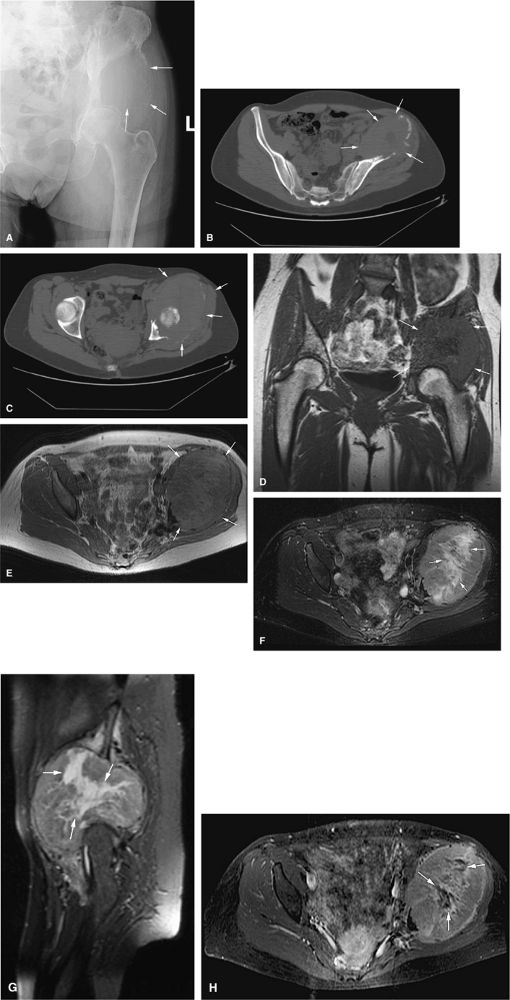

FIGURE 14-78 ● (A and B) Axial CT images showing a large chondrosarcoma arising from the left superior pubic ramus. Punctate calcifications (arrows) are well visualized on the CT images. T2-weighted sagittal (C) and axial (D) images show a large heterogeneous cartilage tumor arising from the left pubic ramus. (E) Axial fat-suppressed T1-weighted contrast-enhanced image shows enhancement in a ring and arc septal pattern.